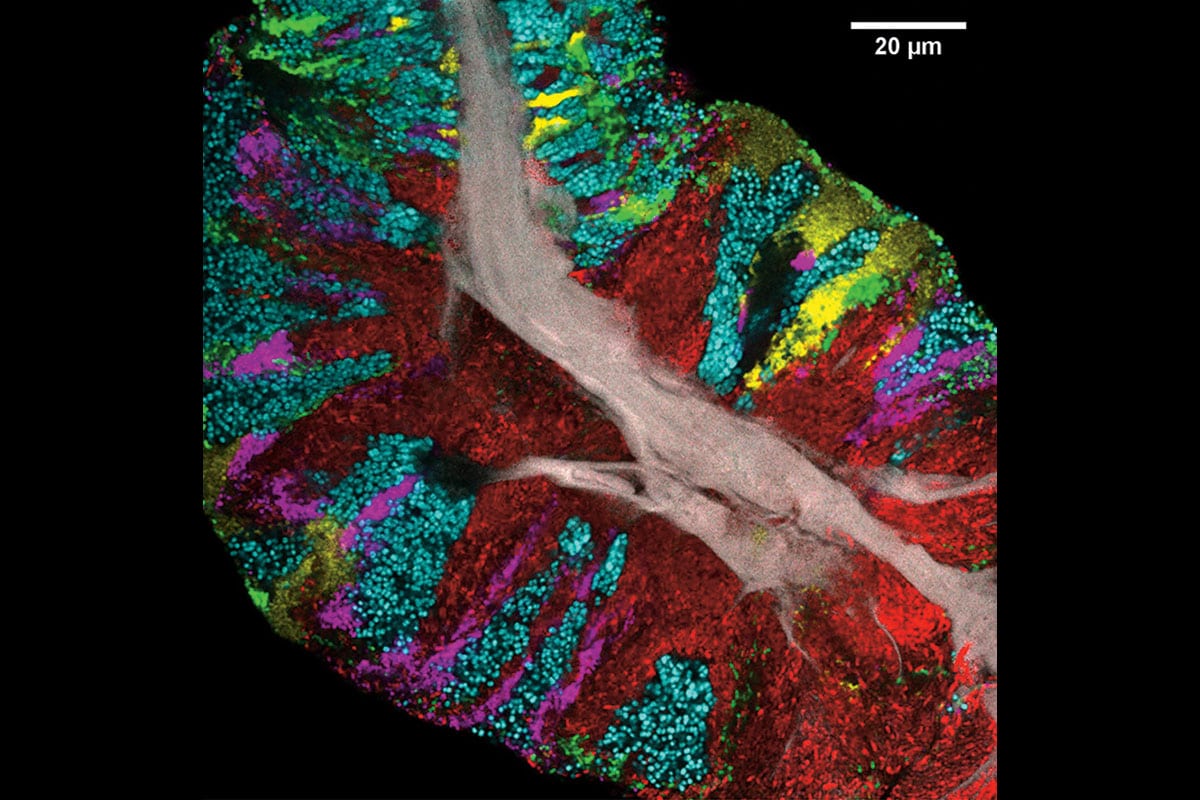

Image: Steven Wilbert et Gary Borisy, Forsyth Institute

Il ne s’agit pas d’une partie de Lite Brite, mais bien de communautés bactériennes sur une langue humaine : chaque genre a sa couleur. Cette image est le résultat de travaux de chercheurs américains qui ont analysé la surface de l’organe du french kiss pour y découvrir une courtepointe organisée. Sur 21 personnes, ils ont utilisé une technique d’imagerie maison pour révéler la structure des groupes en trois dimensions. Le tout a été publié dans la revue Cell Reports .

« Les bactéries sur la langue sont bien plus qu’une simple pile résultant du hasard. Elles ressemblent plutôt à une partie de notre corps », dit Gary Borisy, du Forsyth Institute et de l’École de médecine dentaire de Harvard. En gris est représenté le tissu épithélial, autour duquel les communautés se bâtissent (17 genres sont abondants et prévalent chez les 21 individus testés).

En rouge sont représentées les bactéries du genre Actinomyces ; en vert, les Streptococcus se logent principalement autour de la langue ; en cyan, les bactéries du genre Rothia ; en magenta, les Veillonella ; et en jaune, les Neisseria .